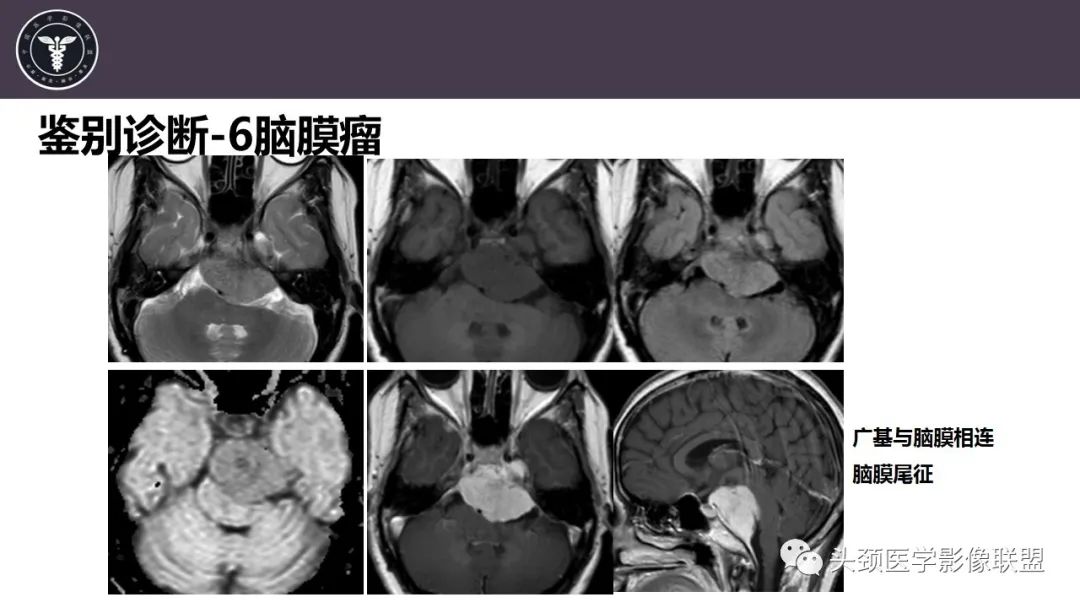

斜坡区骨巨细胞瘤 VS 脊索瘤